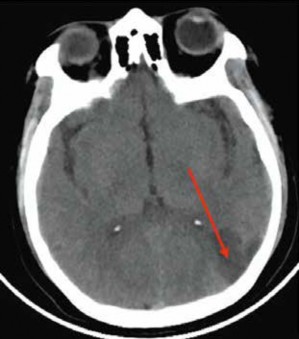

Luego del alta inicia con dificultad respiratoria leve, reportada como cansancio al subir las escaleras, que en sus controles médicos son atribuidos a hiperreactividad bronquial de acuerdo a su antecedente, por lo que es medicada con salbutamol + fluticasona en forma inhalatoria. Sin embargo, la dificultad respiratoria persiste, dos días antes del ingreso se agrega hemianopsia homónima derecha asociada a cefalea; es evaluada por un neurólogo en Moquegua, quien solicita una tomografía cerebral (Figura 1) que evidencia un accidente cerebro vascular de tipo isquémico occipital izquierdo; por tanto es hospitalizada, se agregan antibióticos al manejo terapéutico, pero sin mejoría respiratoria.